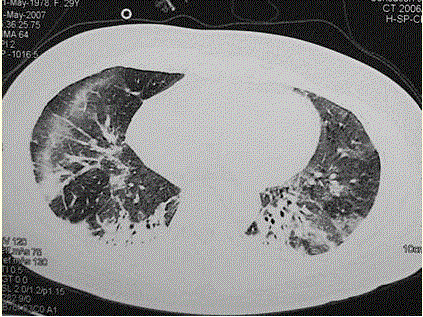

问题  患者女,29岁。间断干咳10年余,加重4个月,伴进行性呼吸困难1个月。病程中出现双手及双足非凹陷性肿胀、双侧膝关节及双侧肘关节对称性肿痛,面部出现细小红色丘疹。体检:T 36.5℃,P 88次/min,R 22次/min,BP 110/75 mmHg,SpO 93%(自然)。额部、前胸及后背散在红色小丘疹,双肺呼吸音增强,双肺中下肺野可闻及爆裂音,右肺明显。胸部CT 如图所示。 下一步处理包括(提示 肺泡灌洗液细胞分类:巨噬细胞41%,淋巴细胞58% ,分叶核细胞1%,经皮肺活检为NSIP富细胞型。)

选项 A、痰找瘤细胞 B、开胸肺活检 C、皮肤活检 D、病理诊断已经明确,直接治疗 E、皮肤活检 F、J0-1抗体 G、检测抗核抗体 H、检测肌酶谱

答案 CEFGH